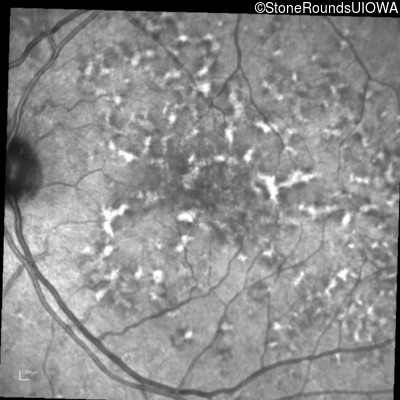

Blue Autofluorescence - Right - 20/20 -1 sc

Exemplar